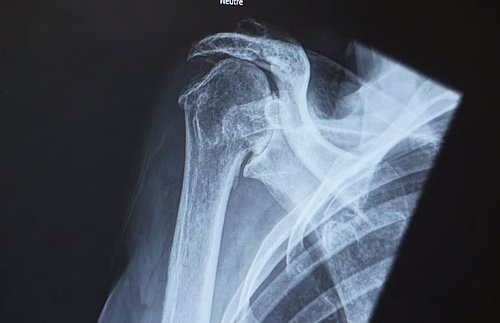

Le pôle ostéoarticulaire et réadaptation réunit des experts de la mobilité et des troubles de la motricité. De la chirurgie orthopédique à la réadaptation, en passant par la neurochirurgie, la chirurgie de la main, la physiothérapie et l'ergothérapie, une équipe complète et multidisciplinaire vous accompagne de la consultation à la rééducation selon vos besoins.